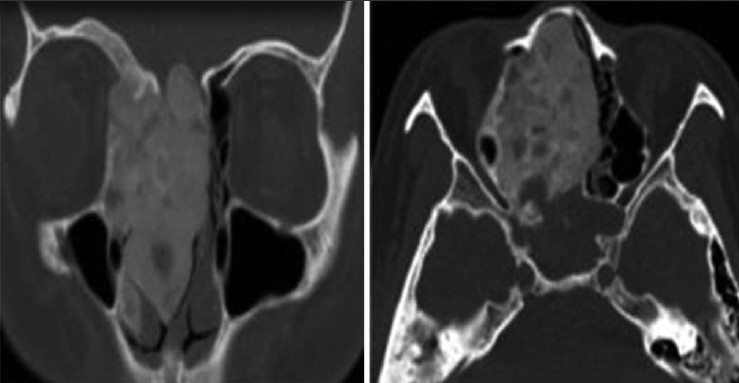

Axial images have a role in the diagnosis of paranasal sinuses problems, but direct coronal scan is better than axial. These results are established by account the number of appearances that showing in coronal view and compared them with those appeared in axial section, where in acute, chronic and fungal sinusitis, the sensitivity of coronal view was (77%, 61% and 61%) respectively compared to axial, which was (22%, 36% and 38%) respectively. In the nasal polyp and granulomatous disease [Figure 2] [Table 1] the efficiency of the coronal view was (62% and 65%), respectively, while in axial was (37% and 34%), respectively. In benign and malignant tumor [Figure 3] and [Figure 4] [Table 2] the efficiency of coronal was 57% and 32% respectively, while in the axial view was (42% and 21%), respectively. | Figure 2: Axial and coronal computed tomography images demonstrate granulomatous disease in a 33-year-old female